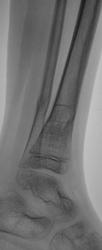

Пол пациента: Женский пол Тип патологии: Травма Область исследования: Скелетно-мышечная система Методы исследования: Rg Снят гипс. Пациент направлен на «контрольные» снимки. Какие мнения будут уважаемые коллеги? https://radiomed.ru/sites/default/files/styles/case_slider_image/public/user/12/2.p8260008.jpg?itok=6w6bzjZb https://radiomed.ru/sites/default/files/styles/case_slider_image/public/user/12/3.p8260006.jpg?itok=o220V7Pk https://radiomed.ru/sites/default/files/styles/case_slider_image/public/user/12/4.p8260007.jpg?itok=JhfzL2sT ID:15021 Вс, 28/08/2011 - 21:04 #1 Vega Не на сайте Был на сайте: 1 день 3 часа назад Зарегистрирован: 22.01.2009 - 19:16 Публикации: 1087 Смещение в вальгус не очень благоприятно, но в данном возрасте допустимо. Не спешить только с полной нагрузкой. Вс, 28/08/2011 - 21:23 #2 Катенёв Валенти... Не на сайте Был на сайте: 7 лет 3 недели назад Зарегистрирован: 22.03.2008 - 22:15 Публикации: 54876 Спасибо Вега! Пнд, 29/08/2011 - 12:29 #3 гаур моника Не на сайте Был на сайте: 14 лет 3 месяцев назад Зарегистрирован: 07.07.2011 - 12:17 Публикации: 27 была травма?????? есле после репозиции то картина хорошая... Пнд, 29/08/2011 - 14:08 #4 Катенёв Валенти... Не на сайте Был на сайте: 7 лет 3 недели назад Зарегистрирован: 22.03.2008 - 22:15 Публикации: 54876 гаур моника wrote: была травма?????? есле после репозиции то картина хорошая... Травма была, репозицию не делали, загипсовали.... Пнд, 29/08/2011 - 14:12 #5 krok Не на сайте Был на сайте: 13 лет 4 месяцев назад Зарегистрирован: 04.08.2011 - 18:13 Публикации: 13 Уважаемый Валентин Львович! Сколько лет юной прелестнице? Геннадий. Пнд, 29/08/2011 - 14:13 #6 Катенёв Валенти... Не на сайте Был на сайте: 7 лет 3 недели назад Зарегистрирован: 22.03.2008 - 22:15 Публикации: 54876 В районе 10-12. Пнд, 29/08/2011 - 14:14 #7 krok Не на сайте Был на сайте: 13 лет 4 месяцев назад Зарегистрирован: 04.08.2011 - 18:13 Публикации: 13 Благодарствую! Геннадий.

Смещение в вальгус не очень благоприятно, но в данном возрасте допустимо. Не спешить только с полной нагрузкой.

была травма?????? есле после репозиции то картина хорошая...

Травма была, репозицию не делали, загипсовали....

В районе 10-12.